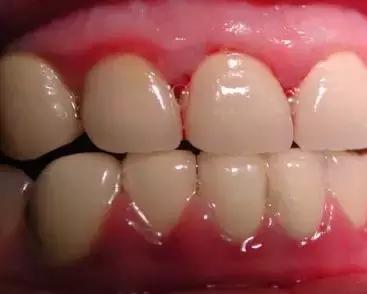

大多数情况都是来自外在的因素(如细菌)导致的出血,比如刷牙不到位导致牙菌斑、牙结石等附着在牙齿表面,长期刺激牙齿周围的牙龈及牙周组织。

虽然起初没有任何的不适症状,但是会使牙龈由健康慢慢变为炎症状态:充血红肿、由坚韧的质地慢慢变得很脆,一旦受到刷牙和咀嚼时的机械摩擦就极易出血。